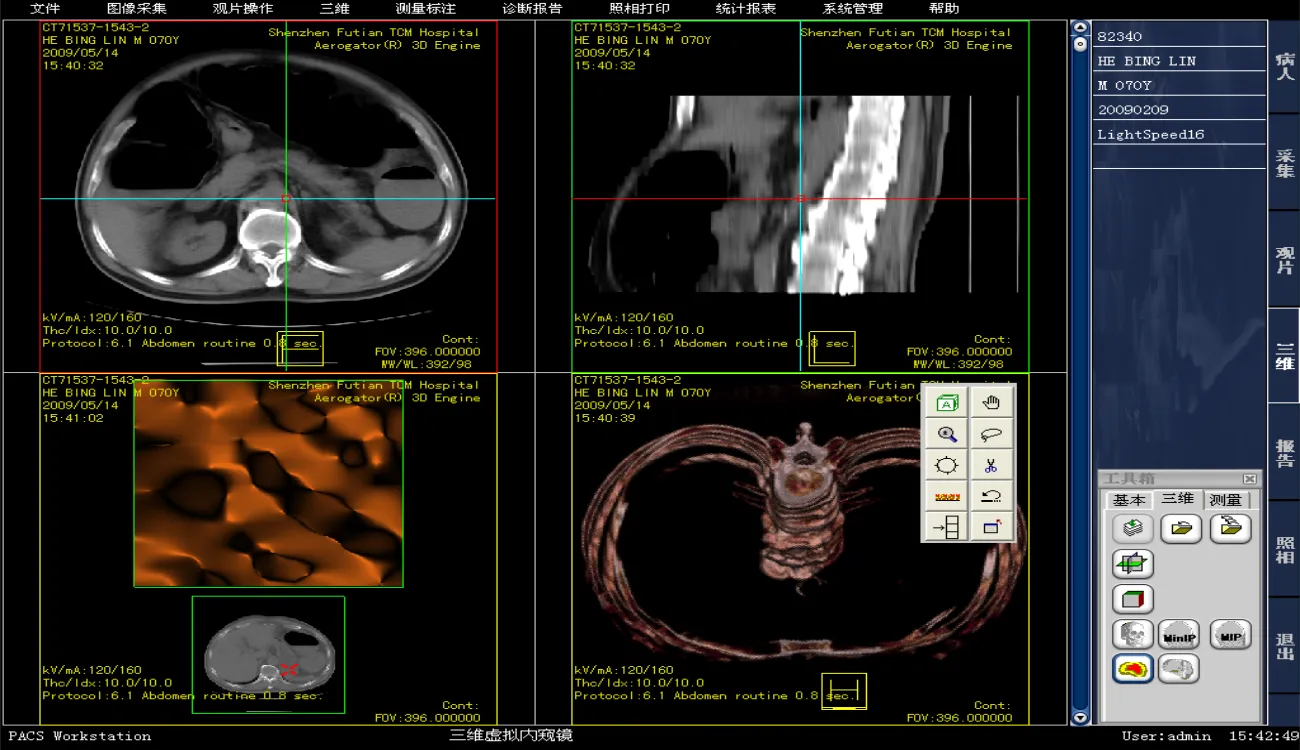

前端与可视化:Web技术 (Vue/React)、医学影像渲染引擎 (Cornerstone.js/VTK.js)、原生技术 (C++/Qt);直接面向医生的“门面”,决定了阅片诊断的效率和体验。

影像渲染引擎:这是Web PACS的技术核心。需要掌握专业的医学影像渲染库,如 Cornerstone.js (用于2D影像渲染和处理)和 VTK.js (用于MPR、VR等三维重建)。

传统C/S架构:部分对性能要求极高的诊断工作站可能仍会采用原生技术,如 C++ 结合 Qt 或 C# 的 WPF,以充分利用硬件资源 。